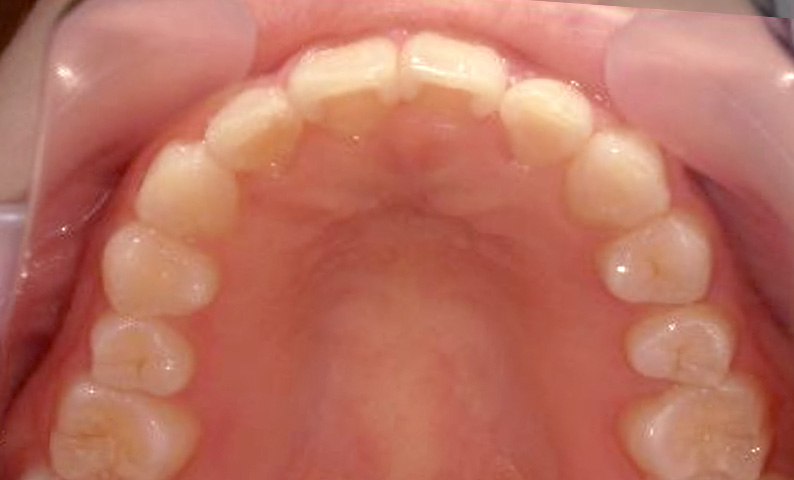

症例_023 上顎だけの部分矯正

治療期間:9ヶ月金額:30万円+税女性前歯のガタガタ上の前歯だけ

| Before | After |

|---|---|

|